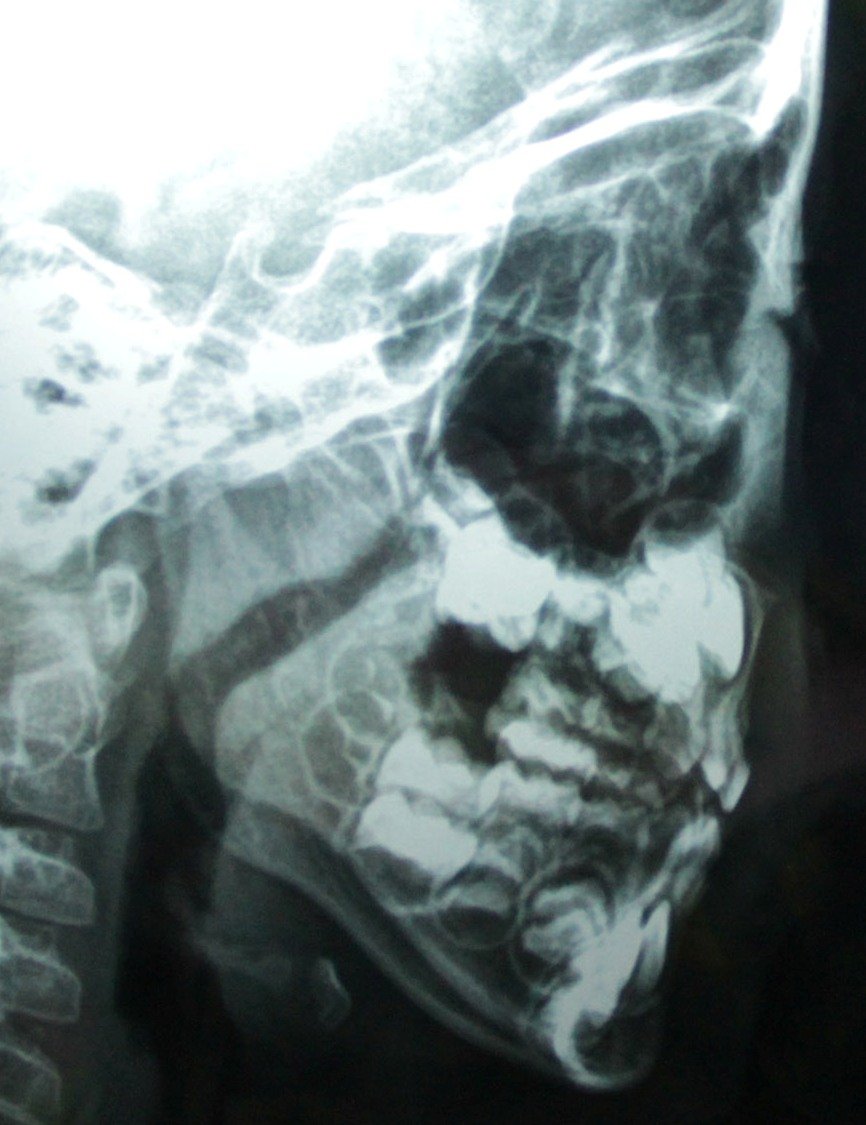

幼儿增殖腺体肥大,怎么治疗? 女孩,三岁,睡觉打鼾,习惯于张嘴呼吸,自感鼻塞,平常玩的时候偶尔鼻子也会发出”呼呼“的声音。今天做了X光,发现腺体肥大。请问我女儿的腺体肥大情况严重吗?用不用手术治疗?如果先保守治疗,用用药,会有效吗? 点击展开 匿名用户 2014-02-21 19:49 为您推荐: 其他回答 睡觉打鼾,习惯于张嘴呼吸,自感鼻塞 孩子身高体重?舌质舌苔颜色?平时手脚冷热?大小便情况?有什么样的饮食起居生活习惯?心情睡眠和运动情况? 温春梅_7INu 2014-02-22 15:30 相关问题 鼻咽部腺体肥大 诊断为宫颈腺体囊肿、宫颈肥大、慢性宫颈… 小儿8岁,经常鼻塞,流鼻涕,睡觉张嘴,打呼噜,检查增殖体肥大,需手术治疗.暑假天气热会影响手术吗?

女孩,三岁,睡觉打鼾,习惯于张嘴呼吸,自感鼻塞,平常玩的时候偶尔鼻子也会发出”呼呼“的声音。今天做了X光,发现腺体肥大。请问我女儿的腺体肥大情况严重吗?用不用手术治疗?如果先保守治疗,用用药,会有效吗?